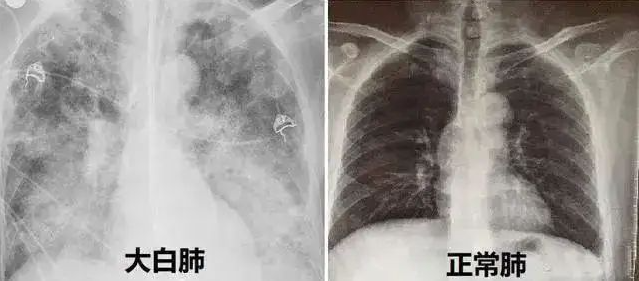

白肺,即急性呼吸窘迫综合征(Acute Respiratory Distress Syndrome,ARDS),是一种严重的肺部炎症反应,通常由感染(如肺炎)、毒素、创伤或其他因素引起。在白肺的情况下,肺泡充满液体或炎症细胞,导致肺部无法有效地进行气体交换,从而导致严重的低氧血症和呼吸困难。